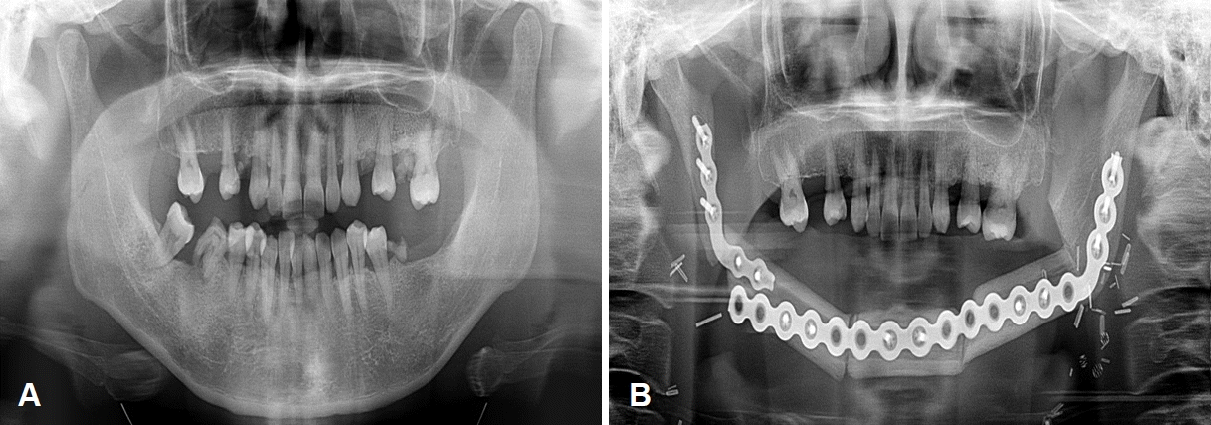

A 45-year-old female with a history of smoking initially presented with painful ulcerative mass at right mouth floor that started 3 months ago (Fig. 1A). This patient was diagnosed with squamous cell carcinoma of mouth floor right (cT4aN2cM0) by punch biopsy and imaging work up. Neck CT and MRI showed a huge irregular mass in the mouth floor and anterior tongue areas. And no distant metastasis was found on PET-CT (Fig. 1B and C). This patient was especially suspected of invading the mandible cortex by MRI and dental scan imaging. We decided to perform a wide excision of mouth floor and anterior tongue with subtotal mandibulectomy, modified radical neck dissection bilateral, tracheostomy and reconstruction with fibular free flap with VSP. Written informed consent was obtained from this patient before surgery. This study was approved by the Institutional Review Board of Yongin Severance Hospital.

The mean total ischemic (the time from vascular pedicle clamping to the completion of vascular anastomosis) and operation time were 102 and 621 minutes. No postoperative complications including flap congestion or necrosis, infection, orocutaneous fistula, hematoma were observed. During follow-up period (13 months), no recurrence was observed by physical examination and imaging work up and the patient was able to have a proper mouth opening and eat a soft diet (Fig. 6). And the patient was very satisfied with postoperatively facial contour.